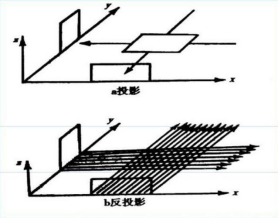

在某一断面,各点的密度值可以看成穿过该平面内该点的射线的投影值的均值,据(1)所得的标定参数,根据两种未知介质的接收情况,利用反投影重建法求出该点的密度,将每一次扫描的数据转化成矩阵进行叠加,结果即为成像图形的灰度像素矩阵。进而成像求解该介质的在正方形托盘中位置,几何形状及吸收率等相关信息,并确定图3中10个点的吸收率。

但是在计算过程中我们可以发现,由于角度的不同,这种叠加过程会使我们在原本没有介质存在的点计算出均值,影响准确度,形成重影,影响各个因素的判断。这种情况称之为星状伪迹。为了修正,我们在问题四中引入卷积反投影法,使所得数据与卷积因子相乘,通过计算,使投影数据值中正负数值相互抵消,根据系统显示的不同矩阵的大小,各投影滤过的原始数据被投影成像并显示出去掉晕伪影的清晰真实图像。

1.基本思想:断层平面成像是有灰度像素点的值大小进行的,也可以说是投影值大小决定的,该平面中某一点的密度函数值可以看作全部经过这一点的X射线的投影值的平均值。然后投影值的平均值即可当作灰度像素进行成像。

因为该CT旋转180次每次1度所以没扫描一次可其余次数得到的投影值联立起来就会构成图形信息,从而达到了图形重构的目的,成像原理如下:

图 5

图 6

5.3.1模型建立与求解

滤波处理模型:如上星状轨迹分析以说明误差和模糊产生原因本模型的目的就是为了将灰度像素矩阵中原本为0和不应该变化的使之变化了,出现边缘失锐效应,需要用对原来的灰度像素矩阵进行有效的滤波,使用滤波函数与灰度像素信号做叠

加运算处理,让灰度像素值再它两旁出现正和负成分,形成所谓的滤波灰度像素值,经过多次数值迭加,可让正和负几乎相互抵消,从而失锐效应消除,最后成像与原像更接近,这种滤波等效于将灰度像素矩阵第i列和进行卷积的到新的滤波矩阵第i列为。

由滤波公式与原来灰度像素矩阵每一列进行卷积,得到了消除边缘失锐的灰度像素矩阵再用原本未滤波的模型进行图形重建运算,程序见附录程序四,结果以及效果如下:

图 14

图 15

图 16